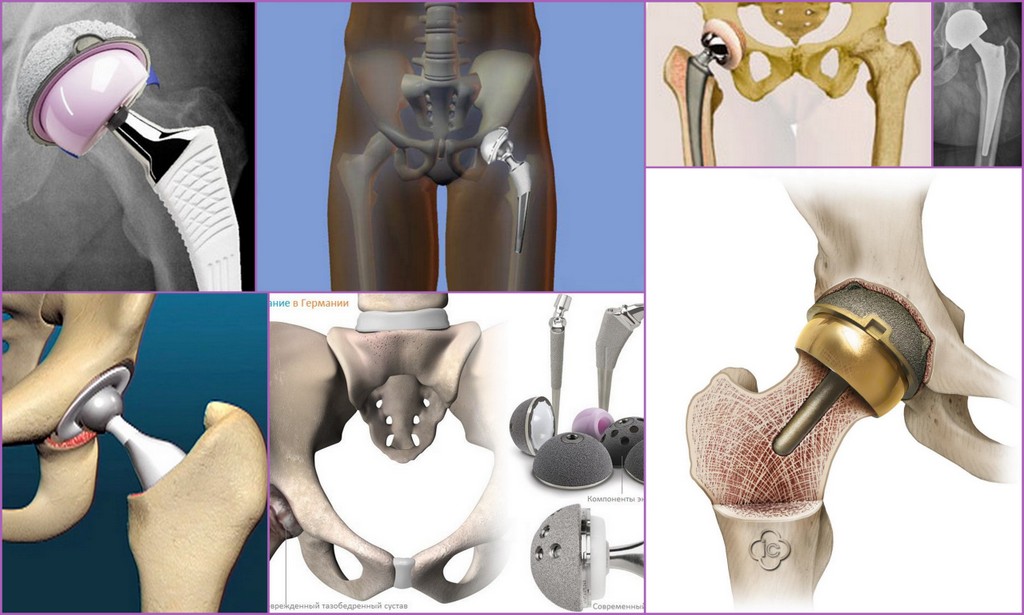

Замена таз сустава

Замена таз сустава 113 фотографий